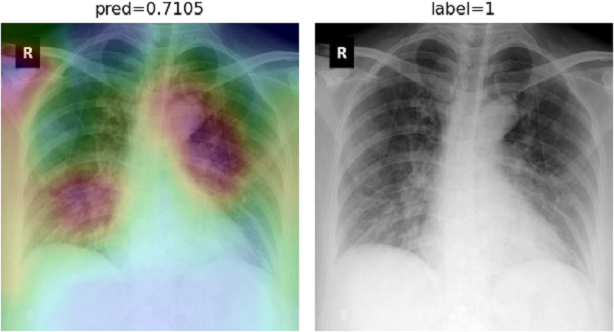

Regarding CheXNet pretrained model, we first probe to see if it is capable of correctly classifying COVID-19 pneumonia with no further improvements. Fig. 14 shows results for two sample CXRs from both classes.

Refer to caption

(a)

(b)

Figure 14: CheXNet probabilities of different classes for (a) a COVID-19 positive case, and (b) a normal case

Extracted heatmaps reveal that CheXNet correctly marks chest lobes to determine each class probability. The output of each class is slightly higher in positive cases for most of the diseases as well. Some of the drawbacks are extremely high predictions for infiltration in most of the dataset images, getting stuck in regions outside lung boundaries and predominantly in corners, and missing some of the opacities particularly in lower lobes.